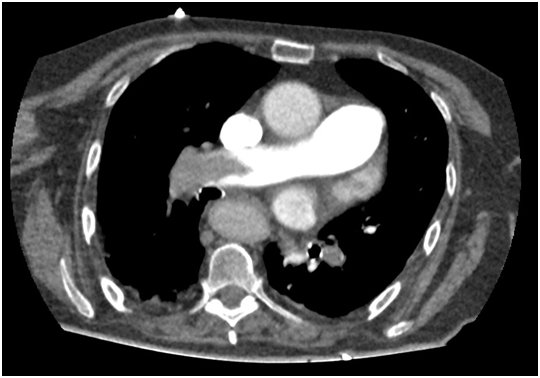

Wells score indicated a high probability of pulmonary embolism, hence anticoagulation with low molecular weight heparin at therapeutic dose was initiated. CT pulmonary angiography revealed filling defects affecting the right main pulmonary artery, right lobar and segmental arteries, left lobar artery and lingular artery, all this findings being compatible with acute pulmonary embolism (Figure 1). Diuretic treatment with Furosemide was optimized and despite all the measures, the dyspnea persisted and oxygen saturation was still low. Therefore, noninvasive ventilation was started. After one hour of therapy, the oxygen saturation values were around 83%, so NIV was substituted by HFNC, reaching a SatO2 of 94% in the following minutes.

Figure 1 CT pulmonary angiography showing acute pulmonary embolism.